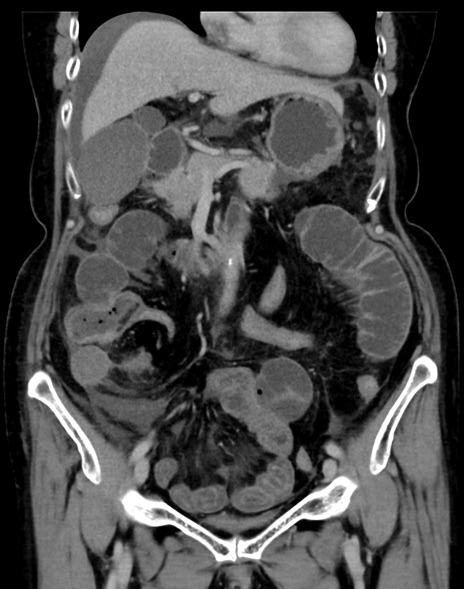

症例13 CT(冠状断像)1日半後